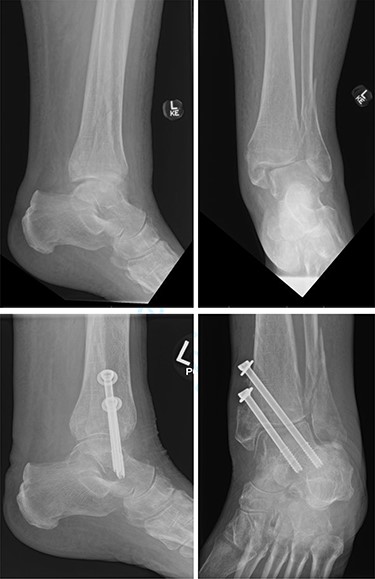

Overall, four out of six patients (66.7%) had satisfactory post-op radiographs with no evidence of talar shift, non/mal-union, widening of the syndesmosis or screw loosening (Figs 1 and 2).

Top—Bimalleolar ankle fracture with talar shift. Bottom—Radiographs at 3 months follow-up showing maintained tibiotalar alignment.